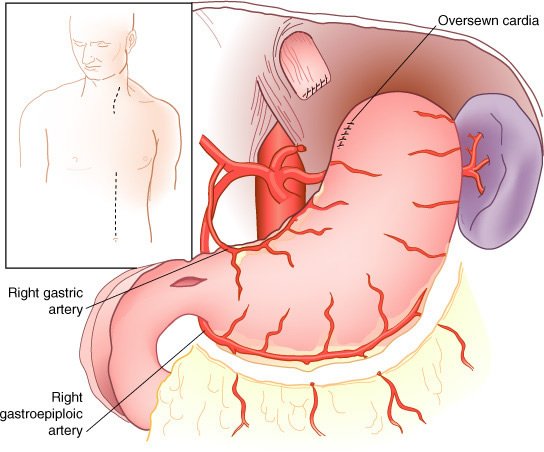

Mobilização do estômago para derivação gástrica subesternal ou substituição esofágica após esofagectomia transiatal. Os vasos gástricos e gastroepiplóicos direitos são preservados, a manobra de Kocher e a piloromiotomia realizadas, e a cárdia seccionada com grampeador e reforço manual. A esofagectomia transiatal é realizada através de uma laparotomia mediana supraumbilical e uma incisão cervical sem toracotomia; entretanto, o esôfago torácico é ressecado atravês da ampliação do hiato diafragmático e do pescoço. O estômago é mobilizado pela secção dos vasos gastroepiplóicos esquerdos e gástricos esquerdos, com preservação das arcadas gastroepiplóica direita e gástrica direita.

Mobilização esofágica durante esofagectomia transiatal sob visualização direta, auxiliada pela ampliação do hiato diafragmático e retração anterior das estruturas mesomediastinais Piloromiotomia e jejunostomia alimentar são realizadas de rotina. Todo o esôfago torácico, do nível das clavículas à cárdia, é ressecado, enquanto há monitoração cuidadosa da pressão intra-arterial para evitar hipotensão prolongada pela mobilização cardíaca durante a dissecção esofágica transiatal .

Após completar a esofagectomia transiatal para tumor localizado no terço distai, é confeccionado o tubo gástrico com o emprego de grampeamento mecânico da grande curvatura, ressecando o máximo de estômago possível distai ao tumor macroscópico. O restante do estômago é, então, posicionado no mediastino posterior no leito esofágico original e anastomosado ao esôfago cervical O grampeador cirúrgico é utilizado para a confecção do tubo gástrico a partir da grande curvatura gástrica com preservação de todo o comprimento.

Após a esofagectomia transiatal e a piloromiotomia, o estômago é mobilizado através do mediastino posterior, o fundo suturado à fascia cervical pré-vertebral, e a esofagogastrostomia término-lateral é, então, realizada

O grampeador é fechado, com aproximação das pás; mas, antes de dispará-lo, realizam-se dois pontos de suspensão em cada lado, entre o estômago anterior e o esôfago adjacente. B, Quando a lâmina do grampeador é avançada, a "parede comum" entre o esôfago e o estômago é seccionada, criando-se uma anastomose ipsilateral de 3 cm de extensão. Então, a sutura dos ângulos é feita em cada lado da gastrotomia. C, A gastroto-mia e o esôfago aberto remanescente são aproximados em duas camadas

O estômago é mobilizado através do mediastino posterior no leito esofagico original e anastomosado (manual ou por grampeamento) ao esôfago cervical.

O estômago normal, adequadamente mobilizado, alcança o pescoço em todos os pacientes.

Esofagectomia torácica total e gastrectomia parcial proximal realizada para adenocarcinoma limitado à junção gastroesofágica e estômago adjacente. Tais tumores podem ser ressecados com uma margem gástrica de 4 a 6 cm, portanto, conservando totalmente a grande curvatura do fundo gástrico e aquele ponto (asterisco) que alcança a porção mais cefálica do pescoço. Uma hemigastrectomia proximal para tal tumor desperdiça esse segmento importante de estômago (área pontilhada) que pode ser utilizada para a reposição esofágica e contribui pouco em uma "operação para câncer".

Para tumores do terço distai do esôfago localizados na cárdia, a pequena curvatura proximal do estômago é ressecada até 4 a 6 cm distai à borda inferior macroscópica do tumor, preservando o ponto da grande curvatura que alcança cranialmente a anastomose com o esôfago cervical. Mesmo carcinomas esofágicos relativamente grandes podem ser ressecados através do hiato ampliado.

Arteriograma do estômago após preparação para substituição esofágica. A rede arterial intramural é vista suficientemente, mesmo após a ressecção da cárdia e da área gástrica esquerda da pequena curvatura

O estômago é o conduto de escolha pela facilidade na mobilização e o amplo aporte vascula).